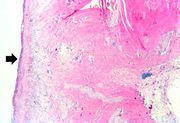

| 04:22, 19 August 2013 | IPLab3BrainInfarction3.jpg (file) | 51 KB | Seung Park | This is a low-power photomicrograph of brain at the edge of the infarct. Note the loss of brain parenchyma (arrows). | 1 | |